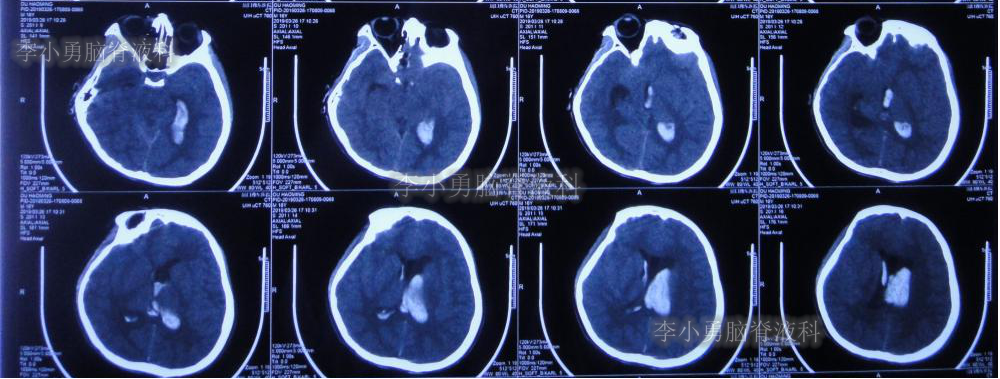

2019年3月26日患者突发头痛及呕吐,随后出现晕厥。急救车送至河南省周口市某医院。行头颅CT(图-1):脑室内出血,次日急诊给予行双侧脑室外引流术(图-2)(第一次的脑室外引流术)。

图-1:2019年3月26日头颅CT:脑室内出血